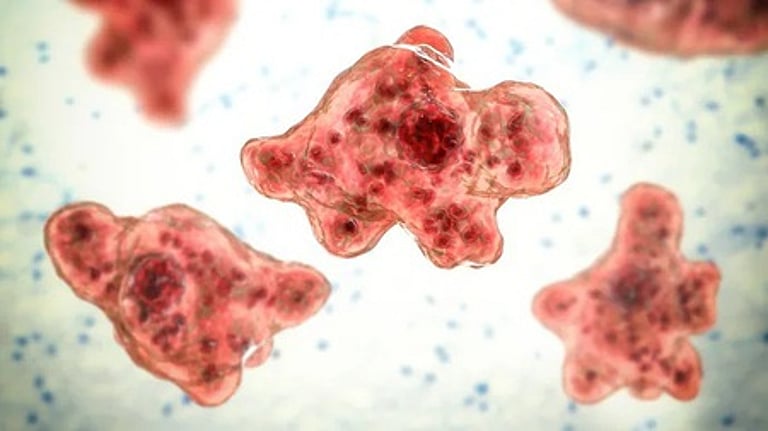

கேரளத்தில் மூளையைத் தின்னும் அமீபா தொற்றால் மேலும் 2 பேர் உயிரிழப்பு! 🕑 Mon, 01 Sep 2025

கேரளத்தில் மூளையைத் தின்னும் அமீபா தொற்றால் மேலும் 2 பேர் உயிரிழப்பு!

கேரளத்தில் மூளையைத் தின்னும் அமீபா தொற்றால் மேலும் இருவர் உயிரிழந்துள்ளனர். ஆகஸ்ட் மாதத்தில் மட்டும் இந்த தொற்றால் உயிரிழந்தவர்களின் எண்ணிக்கை 3